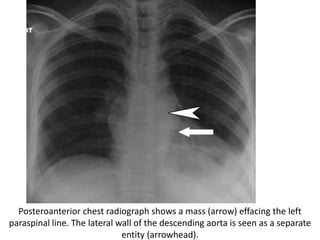

Posteroanterior chest radiograph shows a mass (arrow) effacing the left

paraspinal line. The lateral wall of the descending aorta is seen as a separate

entity (arrowhead).